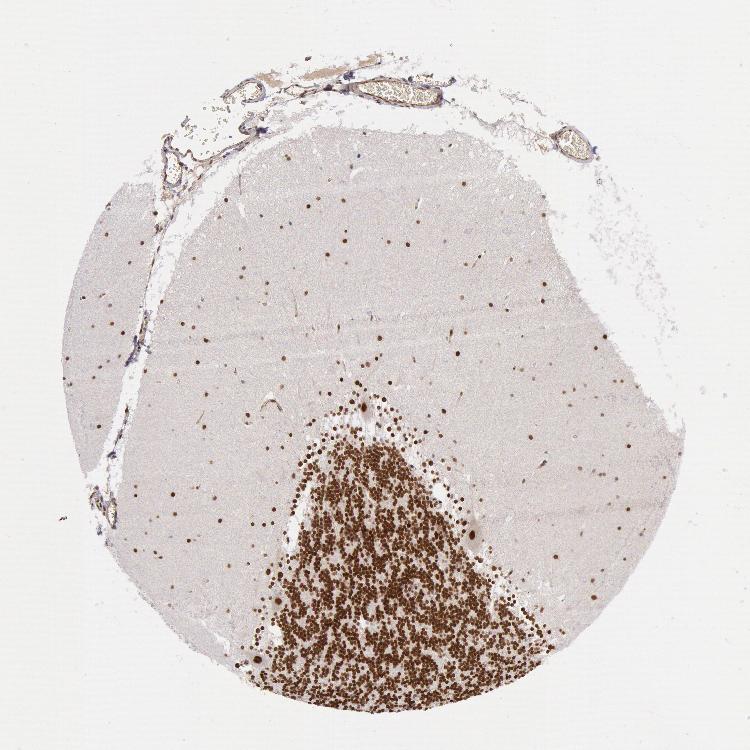

Antibody staining in the annotated cell types in the current human tissue is reported as not detected, low, medium, or high. This score is based on the staining intensity and fraction of stained cells.